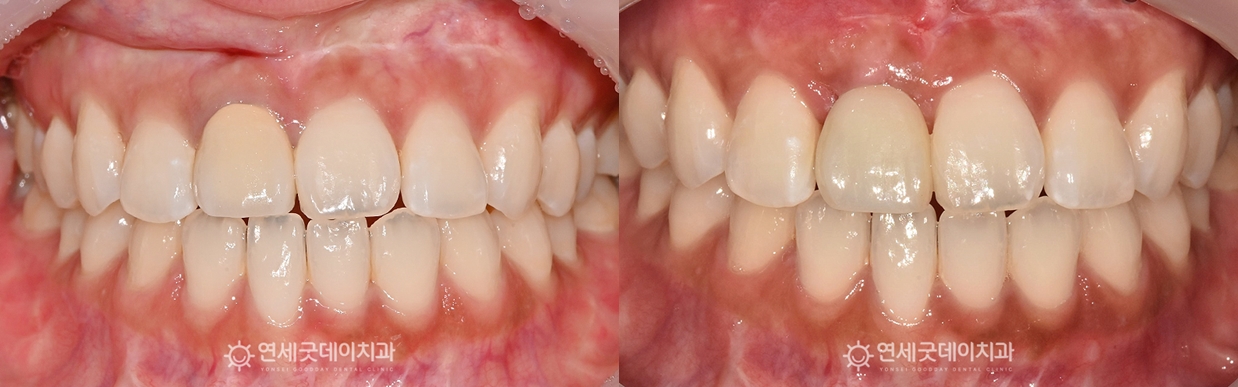

30대 앞니임플란트 치료전후

검게 비어있던 잇몸 부위가 새로운 뼈로 채워지며

이후 지르코니아 크라운을 제작하여 치료를 마무리했습니다. 앞니는 위치상 심미적인 요소에 큰 영향을 미칩니다.

환자분은 아직 젊은 연령이셨기 때문에 앞니 잇몸뼈가 충분히 두툼해졌으며 긴 치료 받으시느라 고생 많으셨습니다 :) ※ 모든 사진은 본인의 동의를 얻어 동일조건에서 촬영하였으며 |